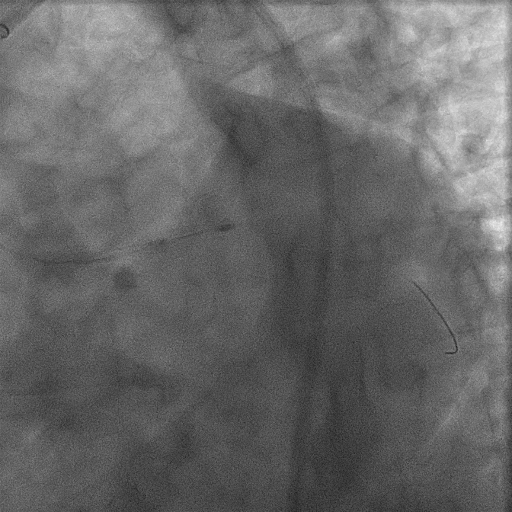

Subsequently, wiring of the LCX artery was attempted. Conventional wiring failed due to a protruding calcified lesion at the LCX ostium. Sequential wiring attempts were made using a Corsair microcatheter(CM, Asahi Intecc Co. Ltd, Aichi, Japan), a SuperCross 90¡Æ catheter(Vascular Solutions, Inc.,Minneapolis, MN), and a Crusade dual-lumen catheter (Kaneka, Japan), but all were unsuccessful. Given the difficulty in crossing, we decided to modify the protruding calcified plaque first by performing rotational atherectomy with a 1.75-mm burr. Following this, wiring was successfully achieved using a GAIA Next 1 guidewire(Asashi Intecc, Japan). Despite successful wiring, plain old balloon angioplasty (POBA) produced suboptimal results. Therefore, an additional rotational atherectomy with a 1.5-mm burr was performed. After successful lesion modification, IVUS of the LCX was obtained, and PCI was completed using a two-stent crush technique using Synergy XD 3.5 x 16 mm for Lt main – pLAD and Synergy XD 3.0 x 16 mm for Lt main - pLCX

Final LAO Caudal.mp4